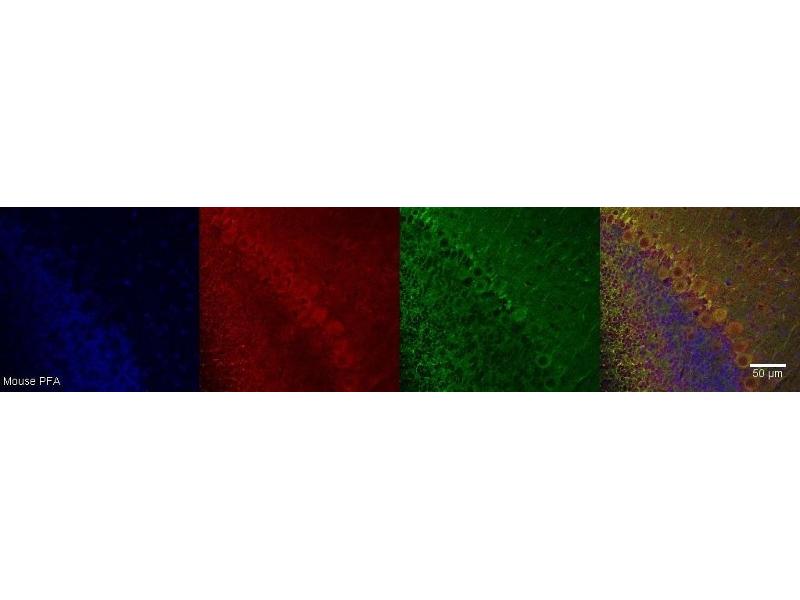

CRHR1 Antikörper

Kurzübersicht für CRHR1 Antikörper (ABIN7456119)

Applikation

- CRHR1

- Monospecific monoclonal antibodies, validated using a next-generation human proteome microarray containing 21,000 full-length and isoform specific purified proteins.